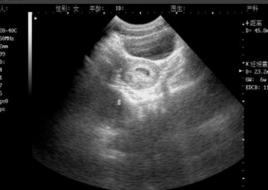

在增大的子宮輪廓內,見到圓形或橢圓形光環,邊界清晰,其內為無回聲區。子宮內出現妊娠囊是超聲診斷中最早期出現的現象,妊娠5周時可以出現,在妊娠囊內可見到有節律的胎心搏動,胚芽和胎動。可確診為早期妊娠、活胎。

受精卵著床後,子宮內膜迅速發生蛻膜變化,蛻膜覆蓋在受精卵之上,把受精卵包圍在子宮肌肉和內膜之間,形成一個封閉的腔隙.受精卵就在這個相對封閉的囊內發育成胎兒,這就是醫學上所稱的 妊娠囊(妊娠囊即 孕囊)。在胚胎髮育早期,羊膜與胚胎形成關係非常密切,而超聲顯示的妊娠囊內充滿的液體,是以絨毛液為主,代表絨毛膜腔,隨著早期妊娠的發展,羊膜腔擴大直至大約孕10周時絨毛腔逐漸消失,羊膜與絨毛膜融合。